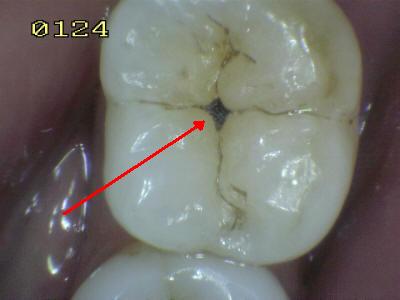

El

cepillado no llega a eliminar las bacterias que se alojan en los

surcos y fosas de premolares y molares. Comenzando el

proceso de desmineralización (Ver secuencia derecha) y creando

una cavidad que compromete la integridad dental. (Ver imagen

izquierda) La evolución

de este tipo de lesión es de solo un par de meses. |

Para

evitar el desarrollo de caries de fosas y surcos es

necesario que el profesional realice los respectivos selladores,

en los surcos y fosas suceptibles. El proceso de

desmineralización en superficie lisas es controlado por medio

del cepillado dental periodico. Y el

uso del hilo dental. Para